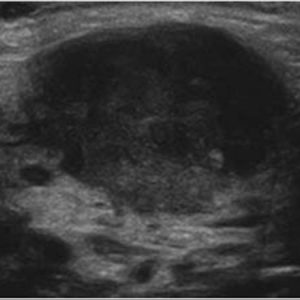

U tuyến nước bọt

Lượt xem: 170» 17-01-2021 -

U tuyến nước bọt

Lượt xem: 174» 17-01-2021 -

U tuyến nước bọt

Lượt xem: 149» 17-01-2021 -

U tuyến nước bọt

Lượt xem: 147» 17-01-2021 -

U tuyến nước bọt

Lượt xem: 146» 17-01-2021 -

U tuyến nước bọt

Lượt xem: 151» 17-01-2021 -

U tuyến nước bọt

Lượt xem: 146» 17-01-2021 -

U tuyến nước bọt

Lượt xem: 136» 17-01-2021 -

U tuyến nước bọt

Lượt xem: 132» 17-01-2021 -

U tuyến nước bọt

Lượt xem: 209» 17-01-2021 -

U tuyến nước bọt

Lượt xem: 150» 17-01-2021 -

U tuyến nước bọt

Lượt xem: 185» 17-01-2021 -

U tuyến nước bọt

Lượt xem: 151» 17-01-2021 -

U tuyến nước bọt

Lượt xem: 212» 17-01-2021 -